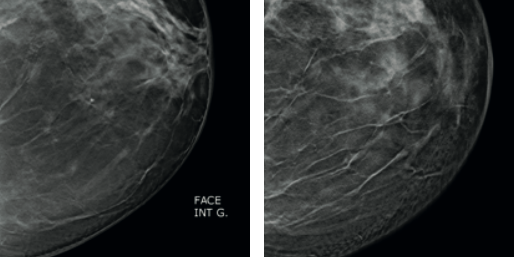

Évolution sur 1 an. Patiente de 56 ans sans antécédents. Apparition en un an d’une tumeur solide développée sur 2 cm.

■ Histologie : CCI de haut grade.

Rappelons que le temps moyen de doublement de volume d’un carcinome canalaire est de l’ordre de trois mois et 10 jours.